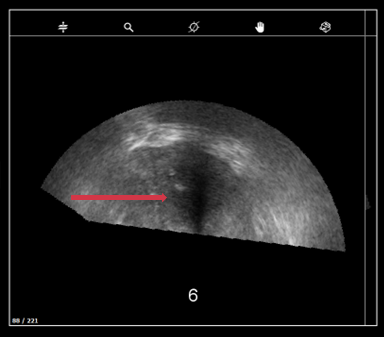

d. Pression sur la sonde et image

- Les lobes dépassent l’image (image de gauche (6)) → déformation de la glande due à une pression excessive sur la prostate).

- Les lignes blanches de la tête de sonde doivent être continues.

- Les images ultrasons ne doivent pas avoir de lignes noires continues(bruit ultrasons).